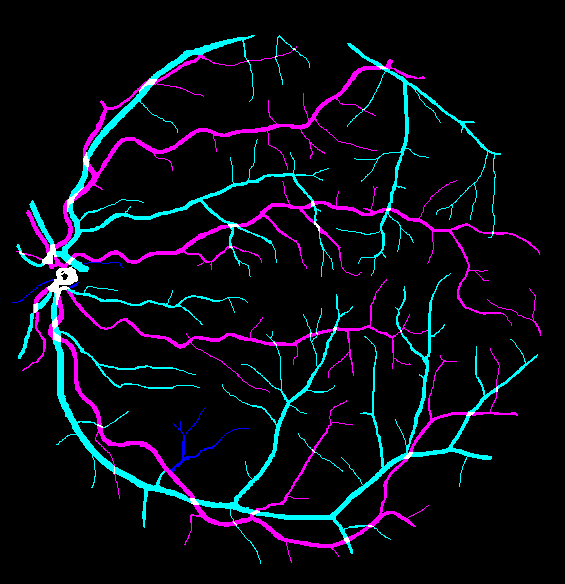

The visual differentiation between arteries and veins can be difficult in some cases, like small vessels with poor contrast and not clearly connected to a specific arterial or venular tree. These cases can be identified with certainty as vessels, but their classification into arteries and veins is uncertain, even for an expert. Additionally, it is common to find crossings between arteries and veins in the retina. Thus, although for these positions either the artery or the vein is above the other, these pixels can be regarded as simultaneously belonging to both types of vessels. This allows to account for continuous arterial and venular trees regardless of crossings below the other one. The identification of these two special situations (uncertain vessels, and vessel crossings) is common in manually annotated retinal vessel classification datasets [38, 42, 43, 44]. Figure 1 shows an example of a ground truth image from the RITE dataset labelled this way, along with its decomposition into arteries, veins, crossings and uncertain vessels.

In addition to this feature, it is also relevant to note that, in this case, the “uncertain” class does not include the vessel crossings, unlike the “uncertain or crossing” class defined in the traditional approach. Instead, in this approach, the vessel crossings are encoded as the superposition of the artery and vein segmentation maps, which should be both indicating positive class for these pixels. In order to do that, the ground truth for each class should be adapted to the output of the network and these restrictions. This can be achieved by considering the vessel crossing regions as positives in both artery and vein segmentation maps, and combining these two maps with the uncertain vessel regions to obtain the vascular tree segmentation map. An example of such an adapted ground truth is shown in Figure 3. Additionally, this setting allows to detect vessel crossings through the intersection (product) of the predicted arteries and veins segmentation masks.

Also, an example of a retinography and its corresponding vasculature segmentation and A/V classification ground truths is depicted in Figure 6.

In order to train the networks following the traditional and MS approaches, the ground truth images from the RITE dataset are adapted, in each case, to the output of the network. In the traditional approach, each pixel of the ground truth is assigned to either background, artery, vein or “uncertain or crossing” class, which comprises both uncertain vessels and crossings. The resulting ground truth is a grayscale image in which each pixel has a numeric label of the class to which it belongs. On the other hand, in the MS approach, each pixel is assigned to any number of the following classes: artery, vein and vessel. In this case, crossings belong to the three classes, and uncertain vessels belong only to the “vessel” class. Background pixels are not assigned to any class. The resulting ground truth is an RGB image in which each channel contains a manual segmentation mask of one of the aforementioned structures. An example of a RITE ground truth adapted to both the traditional and the MS approaches can be found in Figure 7.

Lastly, Figure 13 shows representative examples of the predicted probability maps that were obtained by the trained models using both losses and the enhanced retinographies as input. In each case, the figure depicts the RGB composition of the predicted maps for a better clarity.

In addition to the higher segmentation performance using BCE3, crossings are handled in a more intuitive way. In this case, crossing pixels are simply assigned to both artery and vein classes at a time and the network is able to detect them (see PR curve depicted in Figure 11) while allowing to achieve a continuous segmentation of both the arterial and venular trees. For CE4, differently, the crossings are mostly treated as a separate class (along with the uncertain vessels), either to detect them [39], or to let the network detect the artery or the vein above the other [36, 37, 40, 41]. There is also some approach in which the crossings belong to the same class as that of the upper vessel [38]. Nevertheless, whichever of these alternatives gives raise to incomplete segmentation maps for both arteries and veins. Multiple examples of this effect can be found in Figure 14. Taking all this into account, it can be stated that the MS strategy favors a better segmentation of the different structures, and handles the different cases in a much simpler way.

Another relevant point that can be observed in the different figures is the beneficial effect of the preprocessing for the A/V classification. As can be seen in Table 3 and Figure 12, the performance of the networks is, in general, better when they are trained using the enhanced images than when they are trained using the original ones. In fact, this improvement can be clearly appreciated in Figure 13, which depicts the probability maps that were predicted by the networks for a RITE-test retinography. When comparing the predictions of the “enhanced” and the “original” alternatives, it can be observed that some manifest classification errors disappear, an thus the arteries and veins continuity is slightly better preserved. Regarding the vessels segmentation, in light of the results, the preprocessing does not lead to such a significant improvement in the networks performance.